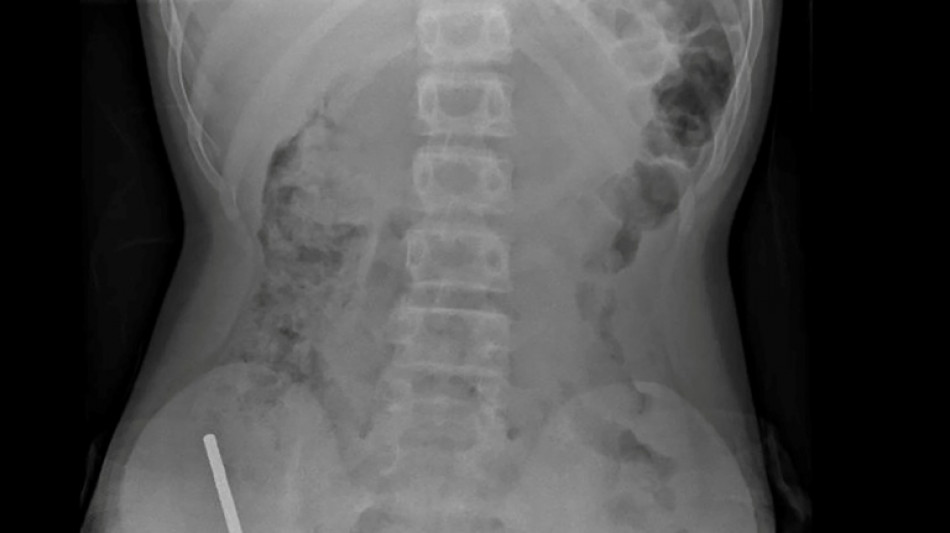

Nouvelle-Zélande: un adolescent opéré après avoir ingéré près de 100 aimants achetés sur Temu / Photo: © NEW ZEALAND MEDICAL JOURNAL (NZMDJ)/AFP

"Il avoué avoir ingéré entre 80 et 100 aimants puissants au néodyme, de 5x2mm environ, une semaine plus tôt", indique un rapport des médecins de l'hôpital de cet hôpital, publié dans le New Zealand Medical Journal (NZMJ).

Les médecins ont déclaré que la pression exercée par les aimants avait provoqué une nécrose dans quatre zones de l'intestin grêle et du gros intestin du garçon.

Il a été opéré afin que l'on lui retire les aimants et les tissus nécrosés, et il a pu rentrer chez lui après huit jours à l'hôpital.